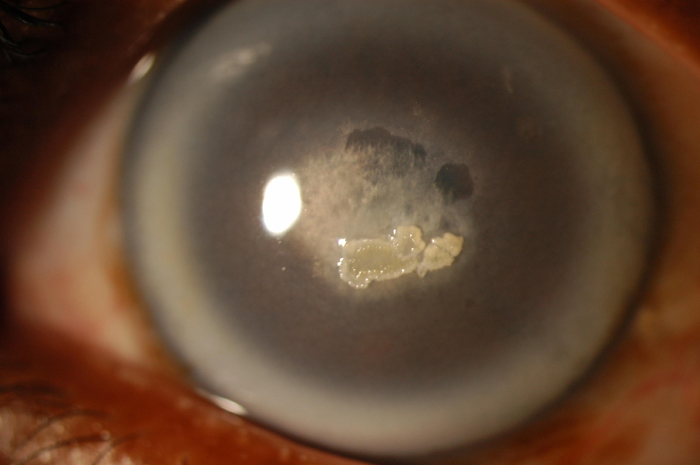

Figure 1. Schnyder crystalline corneal dystrophy

Slit lamp photomicrograph of the proband from a previously unreported family with SCCD demonstrates dense arcus lipoides and central corneal opacification secondary to superficial and subepithelial crystalline deposits. Photograph courtesy of Dr. Sadeer Hannush.